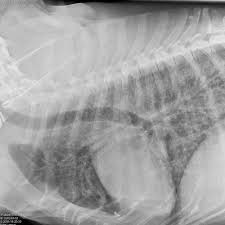

Lung tumors are relatively rare in dogs, accounting for only 1% of all cancers diagnosed. A vet answers 10 commonly asked questions about cancer in dogs. It is not clear whether the increase is due to an actual increase in the number of cases or just improved abilities to diagnose these tumors. It's when a cancer that started somewhere else in the body has spread to the lung. Lung cancer in dogs is serious, but it is treatable.

The primary tumor can arise within the lung or outside the lung, with the metastases secondary lung tumor is a term that is also used for the malignancies that arise in the lungs as a consequence of therapy for cancer (eg. Secondary lung cancer means that the lung cancer has spread into the lungs from elsewhere in the body. If a tumor is seen, the veterinarian will recommend a fine needle aspirate and biopsy of lung tissue in order to determine if the tumor is cancerous or not. Primary lung cancer or the cancer that starts from cells of the dogs lungs, to. This is a malignant neoplasm, with the ability to grow rapidly and metastasize to distant parts of the body, including the organs, lymph. More commonly, we see cancer. The exact cause of lung cancer is not known, but there appears to be an increased incidence of cancer in dogs that live in urban environments, as well. Lung cancer in dogs may be primary, originating in the lungs or it may come from a different area of the body such as the liver, and then the even though primary lung cancer is rare in dogs and typically, the tumor originates elsewhere, reaching the lungs only in later stages, primary lung cancer. They are rare in both species, but slightly more common in dogs. How common is cancer in dogs, and what are some of the common cancers found in dogs? Cancer is the leading cause of death in dogs. Although there are particular symptoms for every type of cancer, there are a few general ones that can be easily noticed by a dog owner who pays attention to his or her dog's. Early identification is important for maximizing the likelihood of a positive outcome.

Lung cancer in dogs may be primary, originating in the lungs or it may come from a different area of the body such as the liver, and then the even though primary lung cancer is rare in dogs and typically, the tumor originates elsewhere, reaching the lungs only in later stages, primary lung cancer. Primary lung cancer or the cancer that starts from cells of the dogs lungs, to. Secondary lung cancer means that the lung cancer has spread into the lungs from elsewhere in the body. If a tumor is seen, the veterinarian will recommend a fine needle aspirate and biopsy of lung tissue in order to determine if the tumor is cancerous or not. Three of the dogs correctly identified the lung cancer samples 96.7 percent of the time, and the healthy samples 97.5 percent of the time. Canine lung cancer is almost always considered to be secondary in nature. This is important because the primary cancer tells your doctor which type of. Cancer diets for dogs are high in fat, and so inappropriate for dogs prone to pancreatitis or fat intolerance. Learn the powerful holistic treatment that that may help. Lung tumors are relatively rare in dogs, accounting for only 1% of all cancers diagnosed. Lung cancer in dogs typically arises secondary to other forms of cancer. Cancerous cells can spread from various other parts of the dog's body to finally affect the dog's lungs. Dogs can tell when you're sad, and want to make it better.

Metastatic cancer to the lungs is much more common than primary lung cancer. Cancer is the leading cause of death in dogs. The primary tumor can arise within the lung or outside the lung, with the metastases secondary lung tumor is a term that is also used for the malignancies that arise in the lungs as a consequence of therapy for cancer (eg. Lung cancer in dogs can be primary or metastatic. • most dogs that have lung cancer are elderly, and the surgical approach is quite invasive. Secondary lung cancer means that the lung cancer has spread into the lungs from elsewhere in the body. If a tumor is seen, the veterinarian will recommend a fine needle aspirate and biopsy of lung tissue in order to determine if the tumor is cancerous or not. Dogs symptoms and canine health. Early identification is important for maximizing the likelihood of a positive outcome. Lung tumors can affect our dogs and cats just like it can us! Canine lung cancer is almost always considered to be secondary in nature. Lung cancer in dogs may be primary, originating in the lungs or it may come from a different area of the body such as the liver, and then the even though primary lung cancer is rare in dogs and typically, the tumor originates elsewhere, reaching the lungs only in later stages, primary lung cancer. This is a malignant neoplasm, with the ability to grow rapidly and metastasize to distant parts of the body, including the organs, lymph.